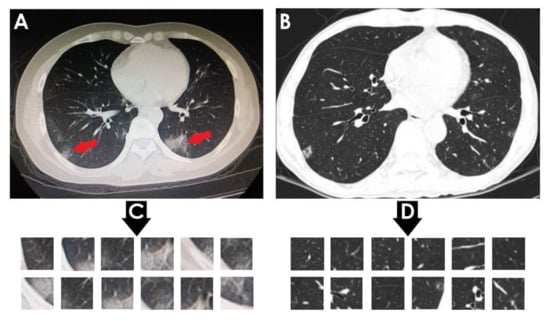

• SARS-CoV-2 CT-scan dataset by [42] from Kaggle (https://www.kaggle.com/plameneduardo/sarscov2-ctscan-dataset) (accessed on 2 December 2021): This dataset contains 2482 CT scan images, which are obtained from 120 patients and divided into 1252 COVID-19 (+) CT images and 1230 COVID-19 (−) CT images. The dataset was collected in 2020 from hospitals in Sao Paulo, Brazil. Figure 2 illustrates the detailed number of patients. The hospitals have not provided detailed characteristics of each patient due to ethical considerations. This dataset is constructed from digital scans of printed CT exams and has no standard image size (the dimensions of the largest images are 416 × 512 while the smallest images are 104 × 119). A comparison of COVID-19 (+) and COVID-19 (−) patients is shown in Figure 3. In Figure 3A, a ground-glass opacity is visible in the lower lobes. In Figure 3B, the chest CT scan shows no abnormalities. The patches that were sampled from infected areas and non-infected areas are shown in Figure 3C,D, respectively.

Figure 3. (A) Shows a CT of the lungs of COVID-19 (+) patient, in which a ground-glass opacity is visible in the lower lobes (red arrows). (B) Represents a CT of the lungs of COVID-19 (−) patient, in which there are no abnormalities. (C) Depicts infected patch samples. (D) Reflects non-infected patch samples. SARS-CoV-2 CT-scan dataset [42] is the source for these images.